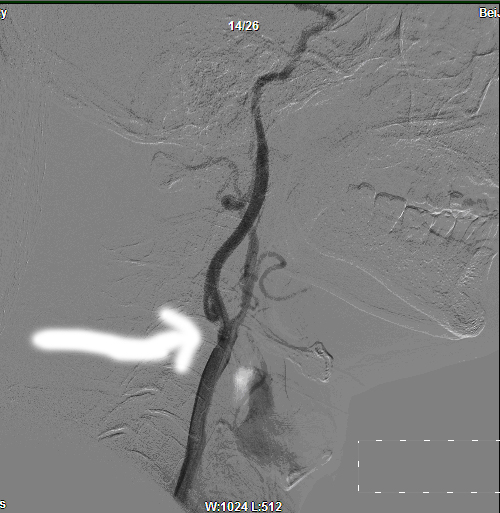

大动脉造影+全脑造影:全脑血管造影血管管壁不规则。双侧颈内动脉中度狭窄(NASCET法)

该患者老年男性,根据ECST法,右侧颈内动脉中度狭窄,有手术指证,于2011年11月11日,张勤奕教授为该患者于全麻下行右颈动脉内膜剥脱术,术后患者恢复良好。